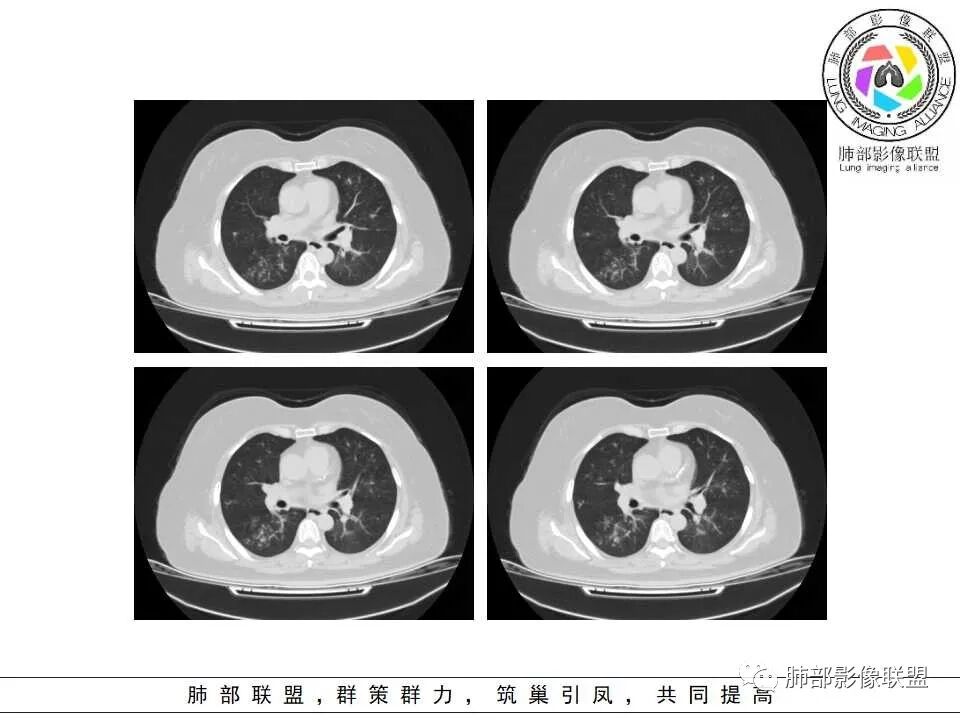

1.病灶沿支气管分布的特点相当明显,相应支气管壁广泛增厚。这种与支气管关系极为密切的片影和/或结节影,常高度提示气道相关感染,如支气管肺炎。

2.患者两肺多发病变,具有广泛性。如此广泛分布更多见于免疫低下的机会性感染。

3.支气管壁广泛增厚对气道侵袭性曲霉病具有一定的提示意义。注意患者没有支气管扩张,临床也未提供IGE等实验室资料。

4.老年女性患者,咳嗽少痰,伴喘息气短8天。注意患者没有发热,中毒症状不明显。既往糖尿病、高血压病史。

炎性指标升高,头孢等药物覆盖疗效不佳。

白细胞升高异乎寻常,注意病史已有两年之久,这至少提供两方面信息:

1)与本次肺部感染不能直接密切对应或相关联,能想象吗,这样的感染持续两年?

2)患者存在血液系统疾病的可能性,如白血病,这应当进一步查实。

1.器官支气管管套样壁增厚和/或支气管扩张,注意壁增厚较均匀,和/或伴有播散性小片影及结节影,注意这些小片影或结节影边界有时较普通炎性病灶清楚。

2.可以阻塞支气管造成肺不张而酷似中央型肺癌。偶而可呈大范围毛玻璃样影。

3.易形成空洞,常无液平面。注意哪些一两周内出现的多发空洞病灶,形成空洞也往往靠边。